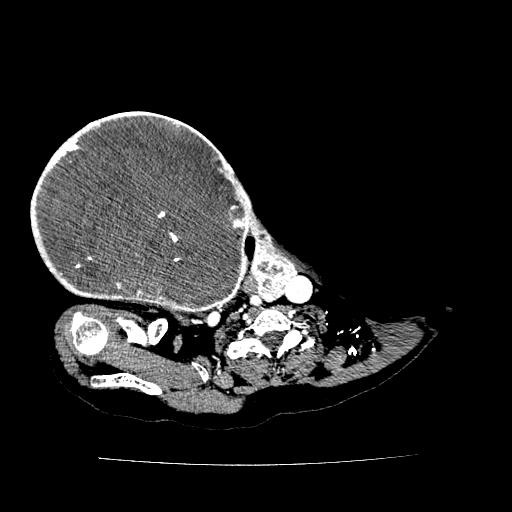

| Phim chụp khối u (BVCC). |

Sau khi được thăm khám và chụp cắt lớp vi tính, bác sĩ cho biết bệnh nhân V.có khối u thùy phải tuyến giáp kích thước 28 x 20 cm.

Theo PGS.TS Lê Văn Quảng cho biết: “Bệnh nhân V. có khối u thùy phải tuyến giáp kích thước rất lớn, tăng sinh mạch máu, đè đẩy khí quản sang bên đối diện, chèn ép động mảnh cảnh, đẩy tĩnh mạch cảnh trong ra ngoài, khối u ở vị trí tập trung nhiều mạch máu quan trọng, u lớn làm tăng sinh mạch máu nên nguy cơ mất máu rất lớn trong quá trình phẫu thuật.Nếu không xử trí tốt có thể gây tổn thương mạch máu lớn, dây thần kinh thanh quản gây khàn tiếng hoặc mở khí quản".